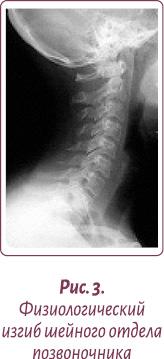

Нормальной статикой шеи считается небольшой физиологический лордоз (прогиб шеи вглубь) (рис. 3).

Шейный отдел позвоночника, состоящий из семи позвонков, должен иметь достаточную длину и определенную статику (рис. 7).

Проведите тесты: проверьте свою шею на статику — нормальный физиологический изгиб (рис. 7).